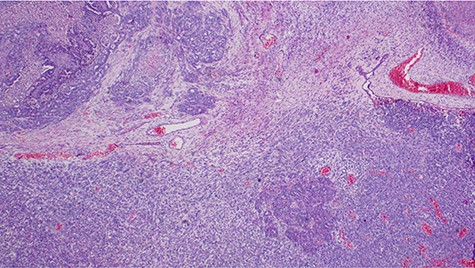

Histopathology of the tumor with malignant epithelial and sarcomatous elements, hematoxylin and eosin, ×100 magnifications.

Malignant mixed Müllerian tumor of the ovary is a rare tumor that accounts for ~1% of all ovarian cancers [1, 2]. These tumors are typically large, ranging from 10–20 cm in diameter; our patient’s tumor was 15.6 × 7.1 × 6.1 cm (Fig. 3). The presence of an intimate admixture of malignant epithelial and stromal elements (Figs 4, 5) is the morphological characteristic feature of this tumor. The epithelial element is most commonly a high-grade serous or endometrioid carcinoma, but can be of any of the surface epithelial cell types of ovarian tumors. The stromal component usually contains sheets of hyperchromatic rounded to spindled cells with marked nuclear atypia and a high mitotic index (Fig. 5). Immunohistochemical stains for epithelial markers are often positive in the sarcomatous component, as it has been observed in the index case (Fig. 6), and their behavior and patterns of spread are similar to high-grade serous carcinomas [3–5].